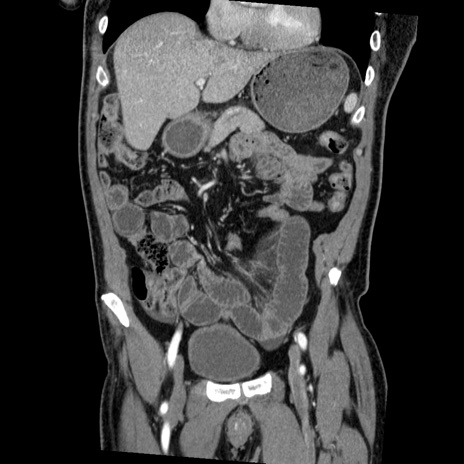

症例22(冠状断像)

【症例】50歳代男性

【主訴】腹痛

【現病歴】AVMからの被殻出血のため回復期リハ病棟入院中。 本日午後3時頃急に下腹部痛が出現した。

【既往歴】AVM、被殻出血、虫垂炎、高血圧

【身体所見】意識晴明、左半身不全麻痺、会話の理解は良好、36.5°C、腹部:膨隆、全体に板状硬、下腹部正中に圧痛点あり、反跳痛-、筋性防御不明、右下腹部にope scar

【データ】WBC 9400、CRP 0.06